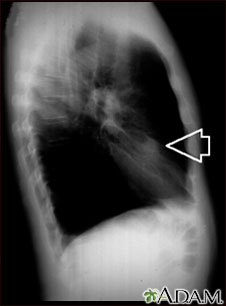

A chest x-ray is an x-ray of the chest, lungs, heart, large arteries, ribs, and diaphragm.

You stand in front of the x-ray machine. You will be told to take a breath in and hold it when the x-ray is taken.

Two images are usually taken. You will first need to stand facing the machine, and then sideways.